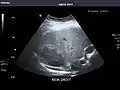

Right kidney

Kidneys: Right and left kidneys measure 11.5 cm and 12 cm in length respectively. No hydronephrosis. Small left lower pole kidney cyst.